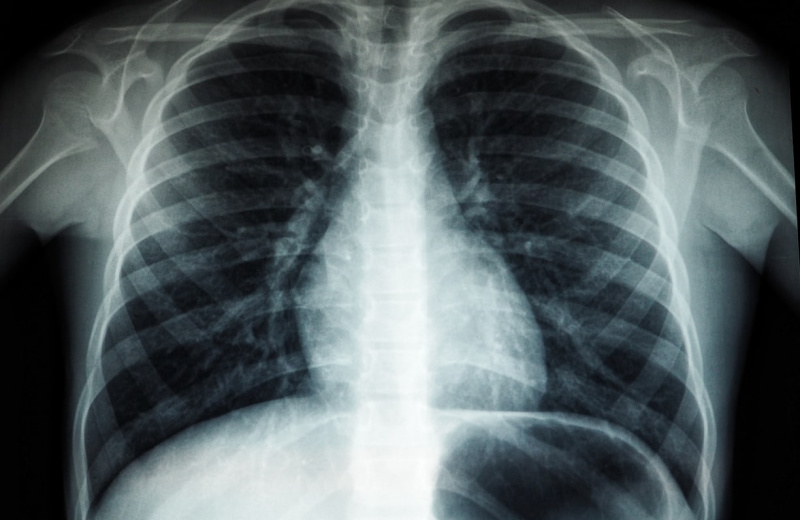

В результате проверки выяснилось, что местная жительница состоит на диспансерном учете в филиале Тенькинская районная больница МОГБУЗ Магаданская областная больница. Согласно закона, на эту пациентку возложена обязанность по прохождению периодических профилактических медицинских осмотров в медицинских организациях. Это необходимо для своевременного диагностирования возможного заболевания туберкулезом.

Однако, последний раз женщина проходила обязательный профилактический осмотр более двух лет назад, что является нарушением установленных норм.

В связи с этим прокуратура подала иск в суд, который обязал женщину пройти медобследование. Это решение суда направлено на защиту здоровья населения и предотвращение распространения инфекционных заболеваний.